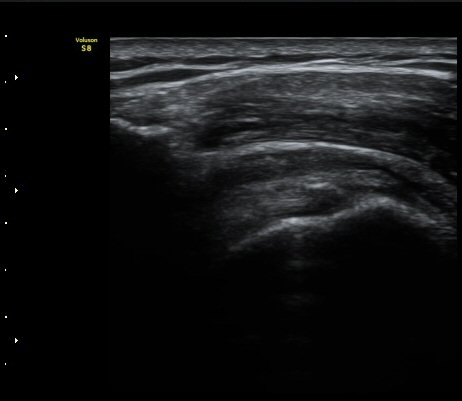

±Ø»ó°Ç ¸»´ÜºÎ Á¾´Ü¸é°Ë»ç¿¡¼­ ±Ø»ó°Ç°ú Á¡¾×³¶³» ¼®È¸È­°¡ °üÂûµÈ´Ù(±×¸² 4, 5).